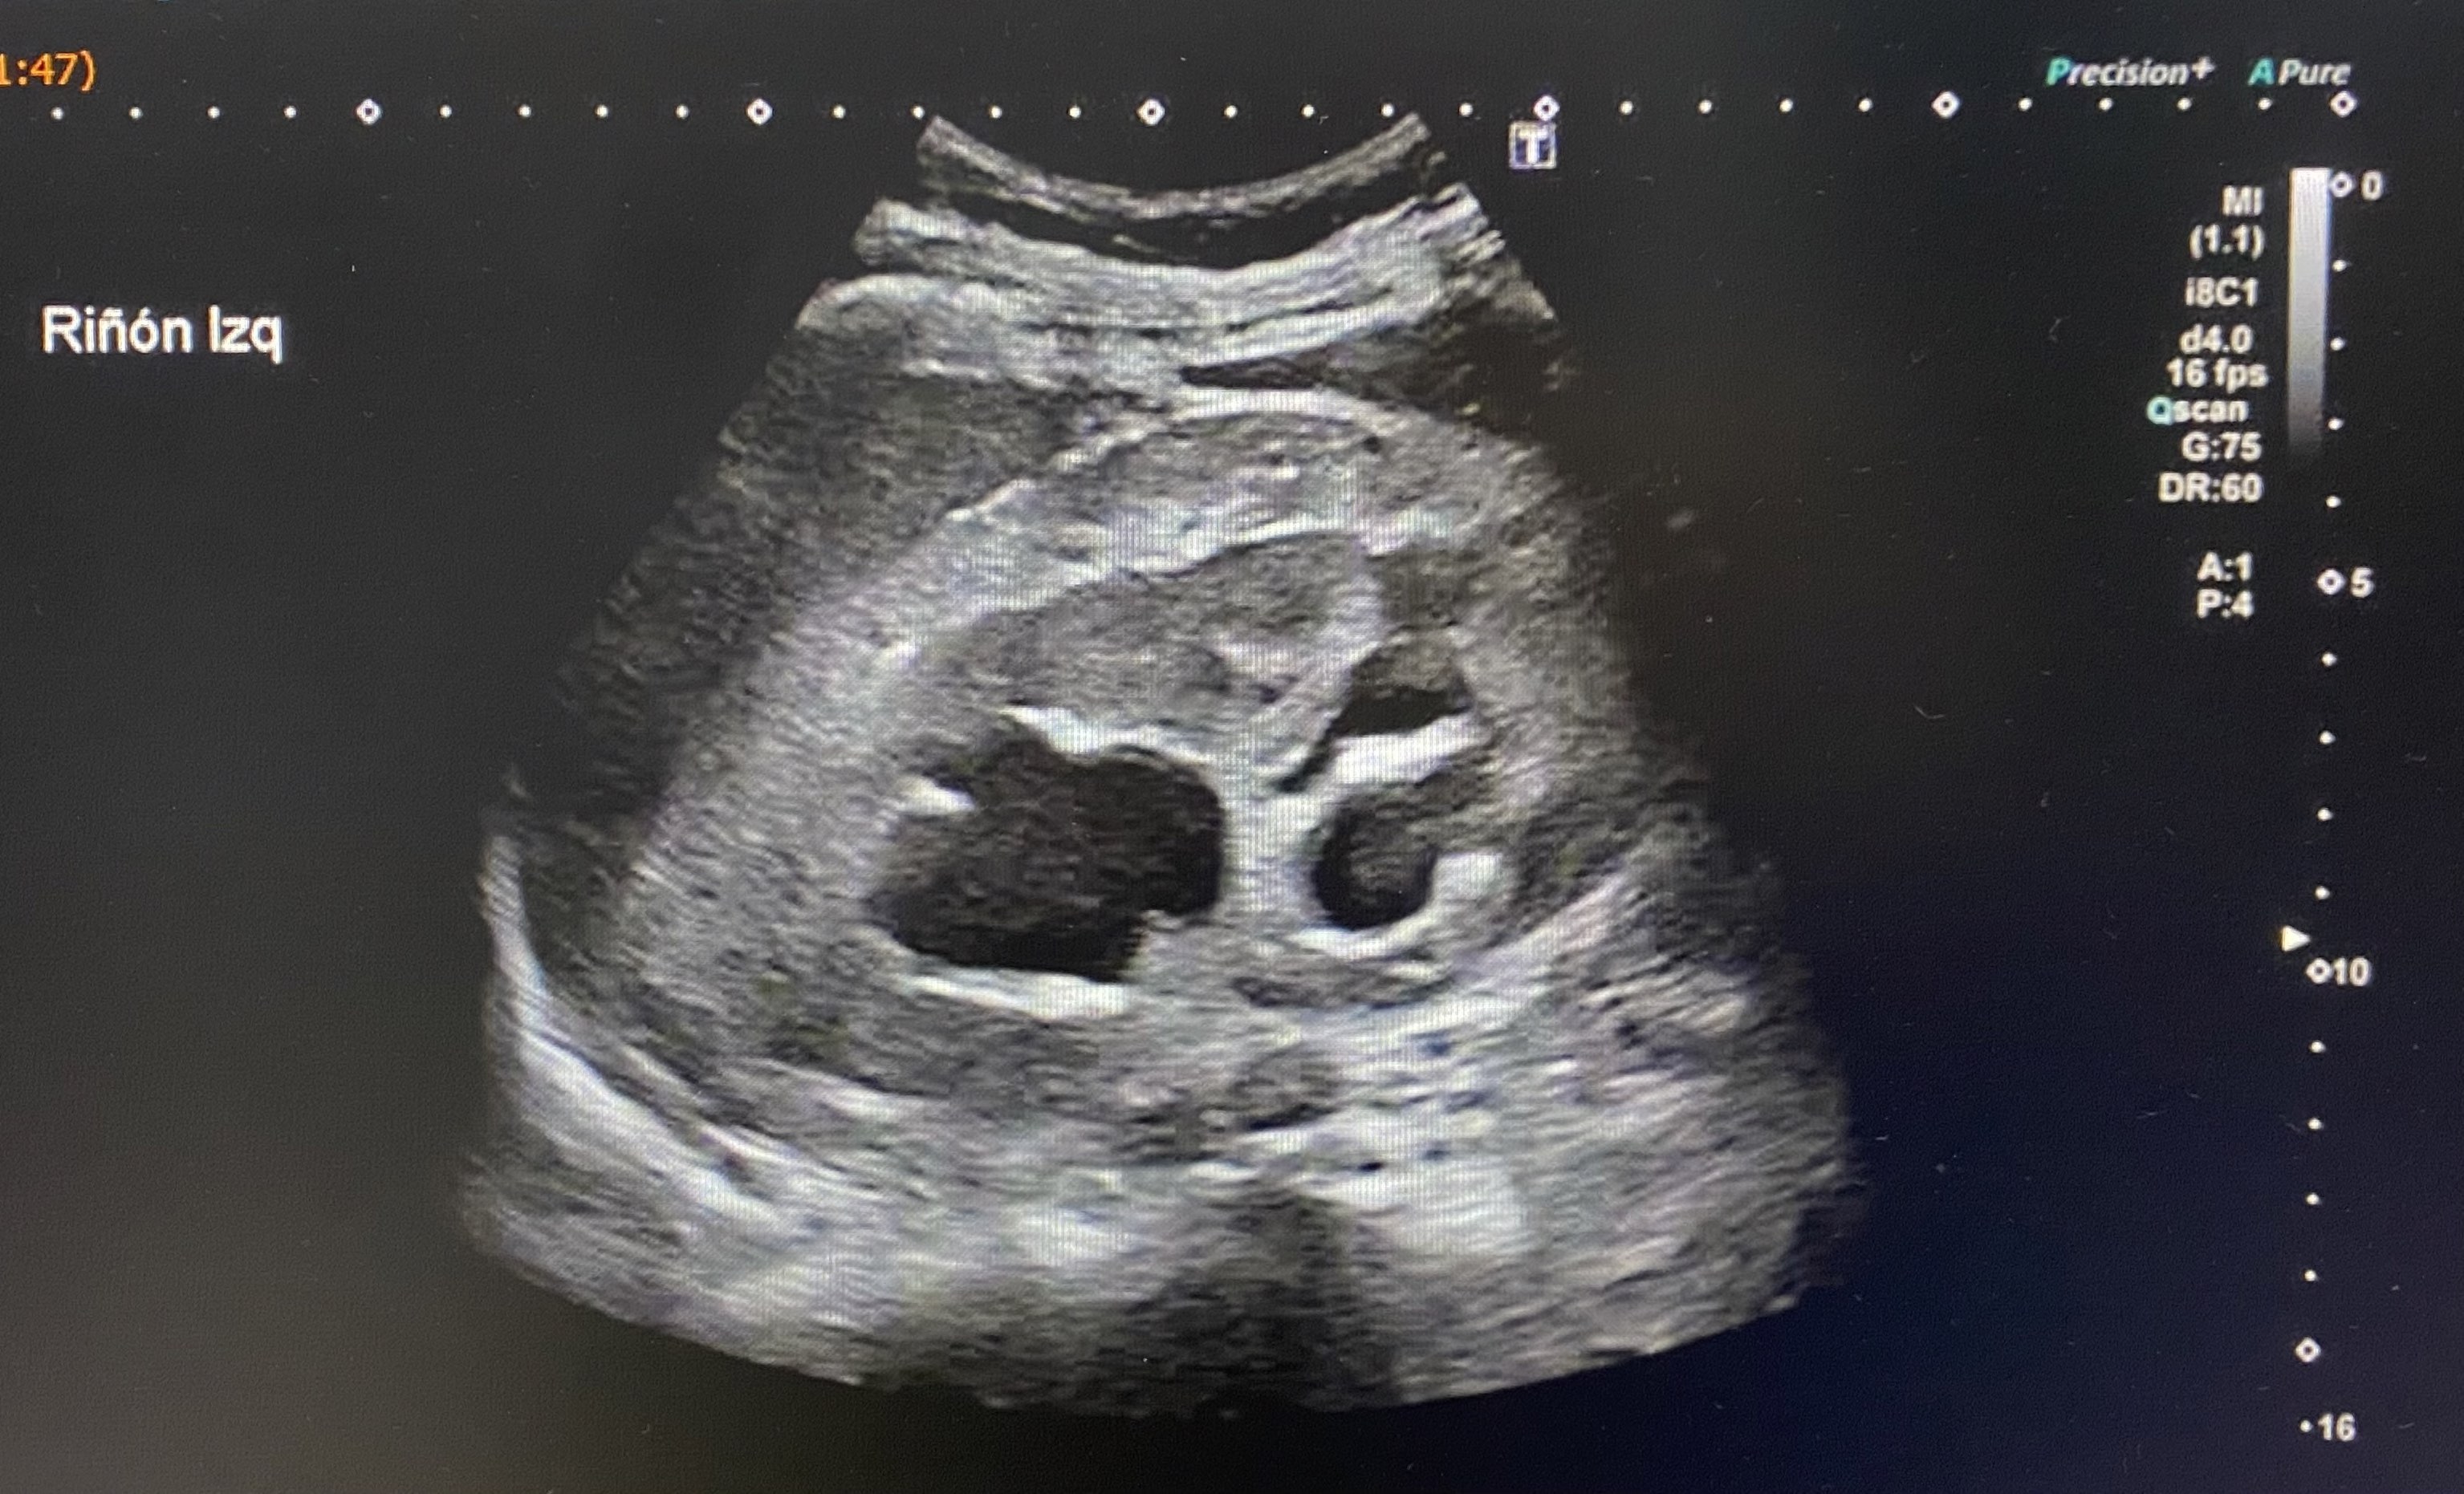

El paciente fue derivado a urgencias hospitalarias para valoración. Se realizó una ecografía a su llegada, observando una marcada distensión vesical (imagen 1) con dilatación pielocalicial y ureteral bilateral, con parénquima renal conservado (imagen 2).